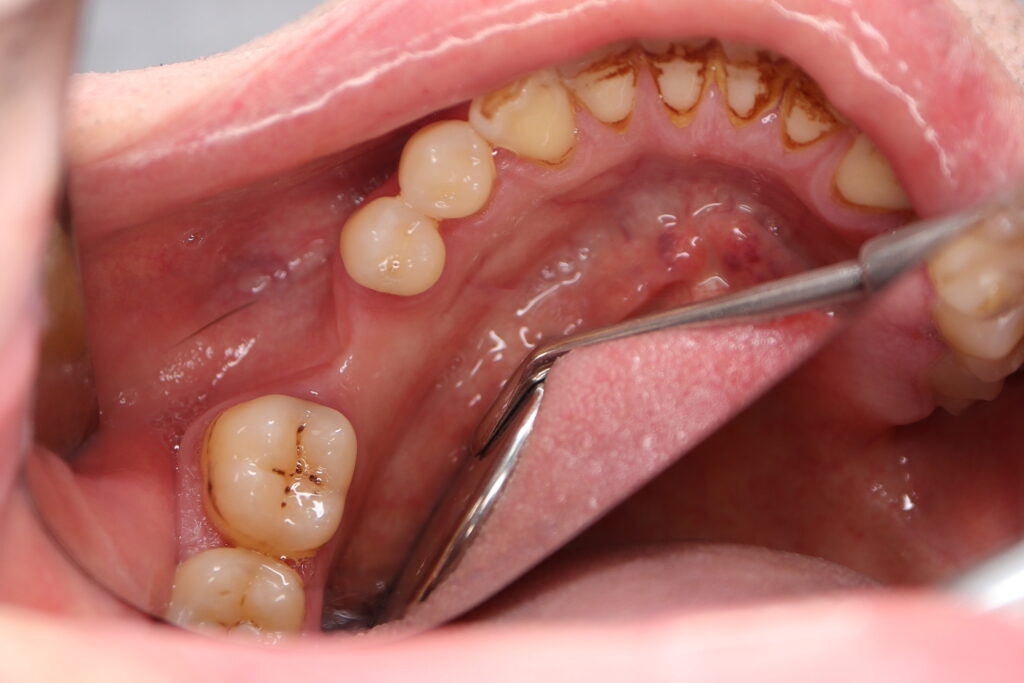

Ситуация до лечения

Пациент обратился с жалобами на эстетические недостатки.

Диагноз: Частичная адентия, клиновидные дефекты, гипоплазия эмали.

пациент до имплантации